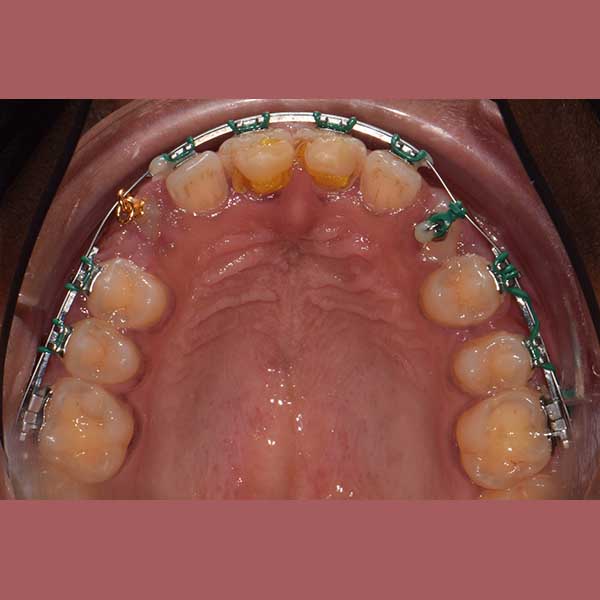

كما تظهر الصور، كانت النتيجة تحولاً جذرياً. تم سحب جميع الأسنان المنطمرة ورصفها في مكانها الطبيعي، وتم تصحيح وضع الأسنان السفلية. في نهاية العلاج، طلبت السيدة بنفسها وبكل ثقة أخذ صورة لابتسامتها الجديدة التي طالما حلمت بها.